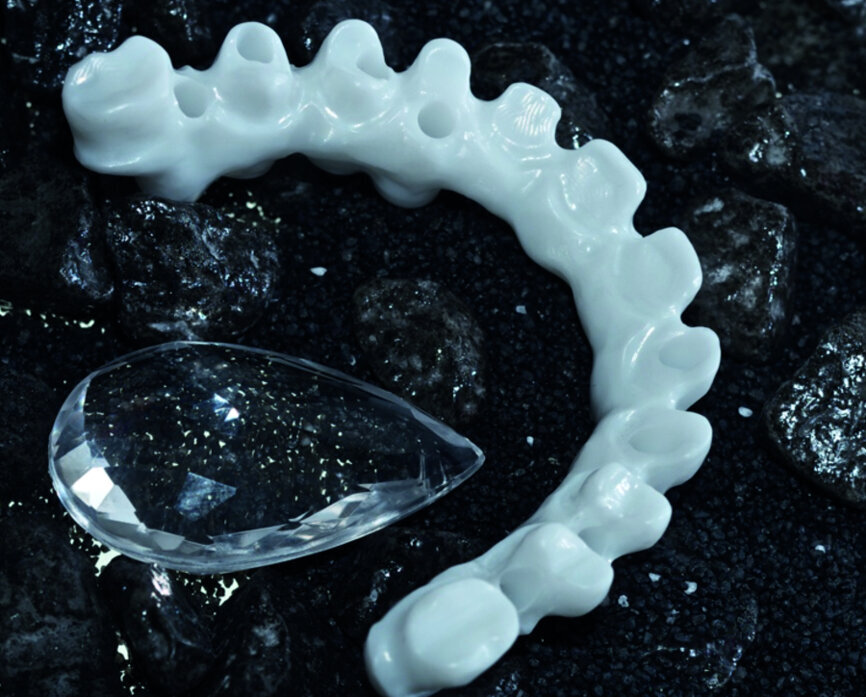

Figure 5 : Bridge en « full zircone maquillée », à noter le collage intraarmature de bague en titane, afin d’assurer une interface titane/titane entre les implants et le bridge.